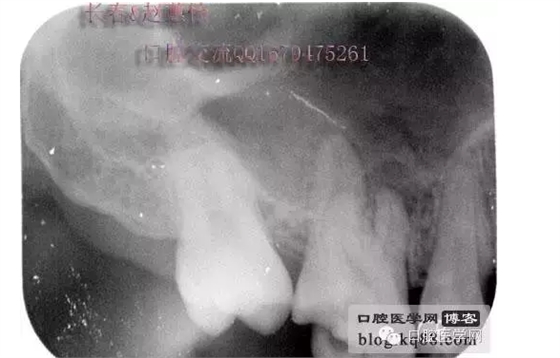

這個(gè)是術(shù)前照片,一切如常

患牙是死髓牙,患者是一位大學(xué)生,探查根管時(shí)一切都很順利,就有點(diǎn)忽視了,當(dāng)然這個(gè)臺(tái)階是人為造成的,造成的原因呢就是使用機(jī)擴(kuò)時(shí)跳號(hào)了,所以大家一定要逐號(hào)使用啊,預(yù)備出一個(gè)臺(tái)階,后續(xù)要搭上很長時(shí)間才能搞定,好不容易越過臺(tái)階下去的銼,一提拉出來就下不去了,著實(shí)讓人郁悶,一切都要從頭再來,這個(gè)時(shí)候再下銼的時(shí)候就必須預(yù)彎了。而且要多角度試探,很是考驗(yàn)?zāi)托牡臅r(shí)候。吃一塹長一智嘛!